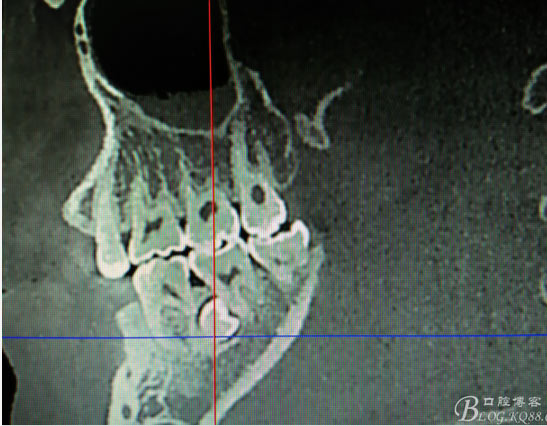

患者、盧xx、男、19歲。主訴:左側(cè)下頜乳磨牙未脫落,要求檢查。??茩z查:左側(cè)下頜第二乳磨牙有充填物。無松動,全景片檢查。35移位至36、37之間。頰舌側(cè)均不能觸及隆起。CBCT檢查:35位于36、37的舌側(cè)。表面骨質(zhì)約2mm左右。35完全骨埋伏,36的遠(yuǎn)中牙根疑是吸收。建議35暫觀察。置留不取?;颊咭蟀纬龘?dān)心壓迫36牙根或者發(fā)生囊性變。術(shù)前簽手術(shù)同意書。

圖1.術(shù)前的全景片影像檢查,35移位至36、37之間。